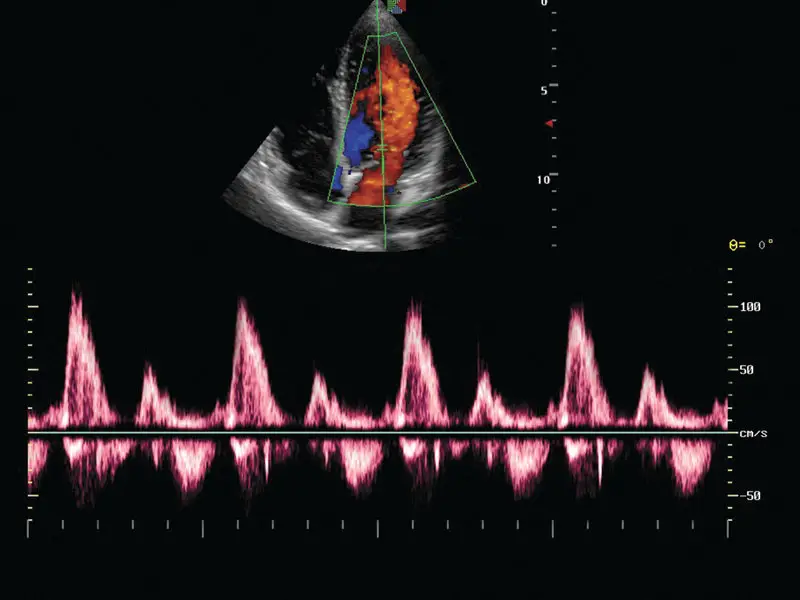

L’échographie et l’échocardiographie jouent un rôle clé en médecine vétérinaire pour examiner en profondeur les organes internes de votre animal. L’échographie permet d’explorer le foie, les reins, la vessie et d’autres structures internes, afin de diagnostiquer diverses pathologies sans recours à des procédures invasives. L’échocardiographie, quant à elle, est indispensable pour évaluer la santé du cœur, notamment dans le cadre du suivi des maladies cardiaques comme les maladies dégénératives de la valve mitrale ou pour détecter des malformations cardiaques congénitales.

L’acquisition des technologies Doppler pulsé, continu et couleur en imagerie cardiaque est une avancée majeure. Ces techniques permettent de mesurer le flux sanguin et d’évaluer la circulation dans les vaisseaux et à travers les valves cardiaques. Le Doppler pulsé et continu aident à quantifier la vitesse du flux sanguin, tandis que le Doppler couleur offre une visualisation précise des anomalies du flux, essentielles pour détecter des fuites valvulaires, des rétrécissements ou des malformations. Ces outils améliorent considérablement le diagnostic et le suivi des maladies cardiaques de votre animal, permettant une prise en charge plus rapide et plus efficace.